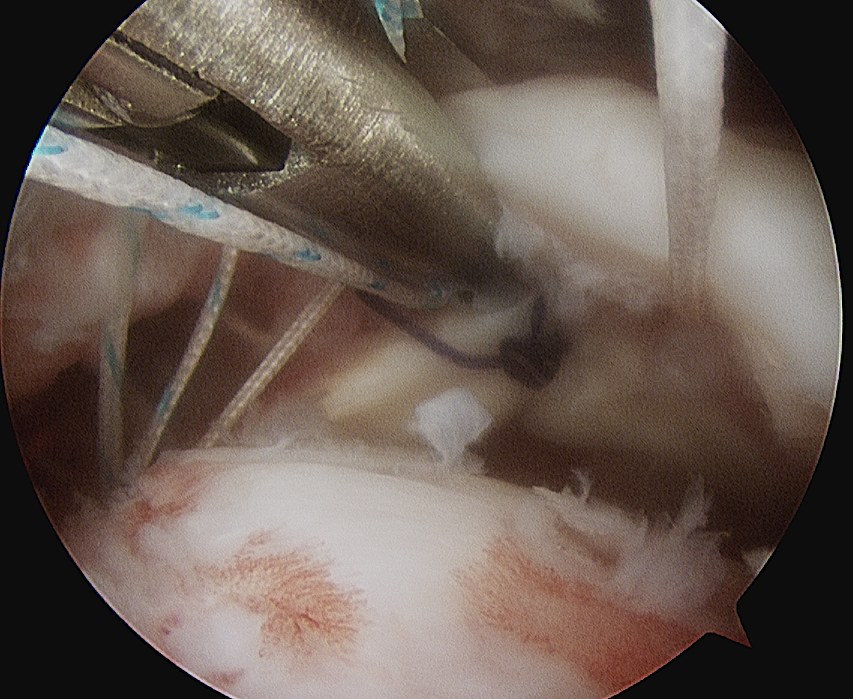

- insert anchors (retract port of Wilminton into subacromial space)

- pass sutures with suture passer

- tie